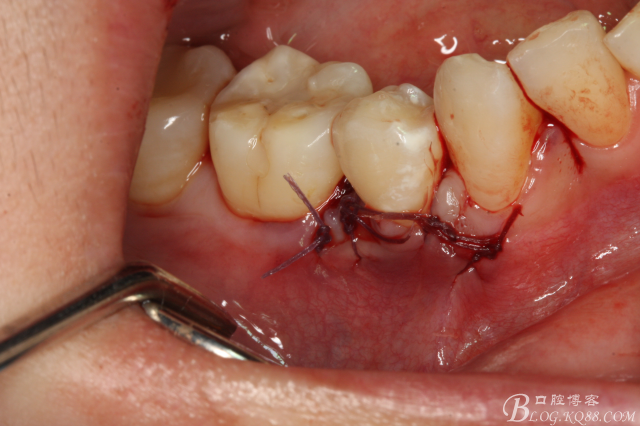

圖19.縫合